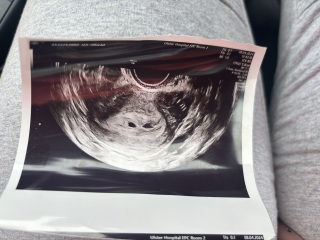

Following a ectopic pregnancy in December and right tube removal, I found out I was pregnant last week and have being seen by early pregnancy.I am 5 weeks 1 day. Theres 2 sacs but the nurse didn’t seem to mention the second one said it could be a sac or could be fluid and didn’t focus on it. Has anyone else ever had this?

Yes was back for a scan on Sunday and 2nd sac is completely empty but the other one has embryo with a heartbeat. Could have being a second pregnancy sac but they can’t say for sure. Early pregnancy nurse said the empty sac should absorb